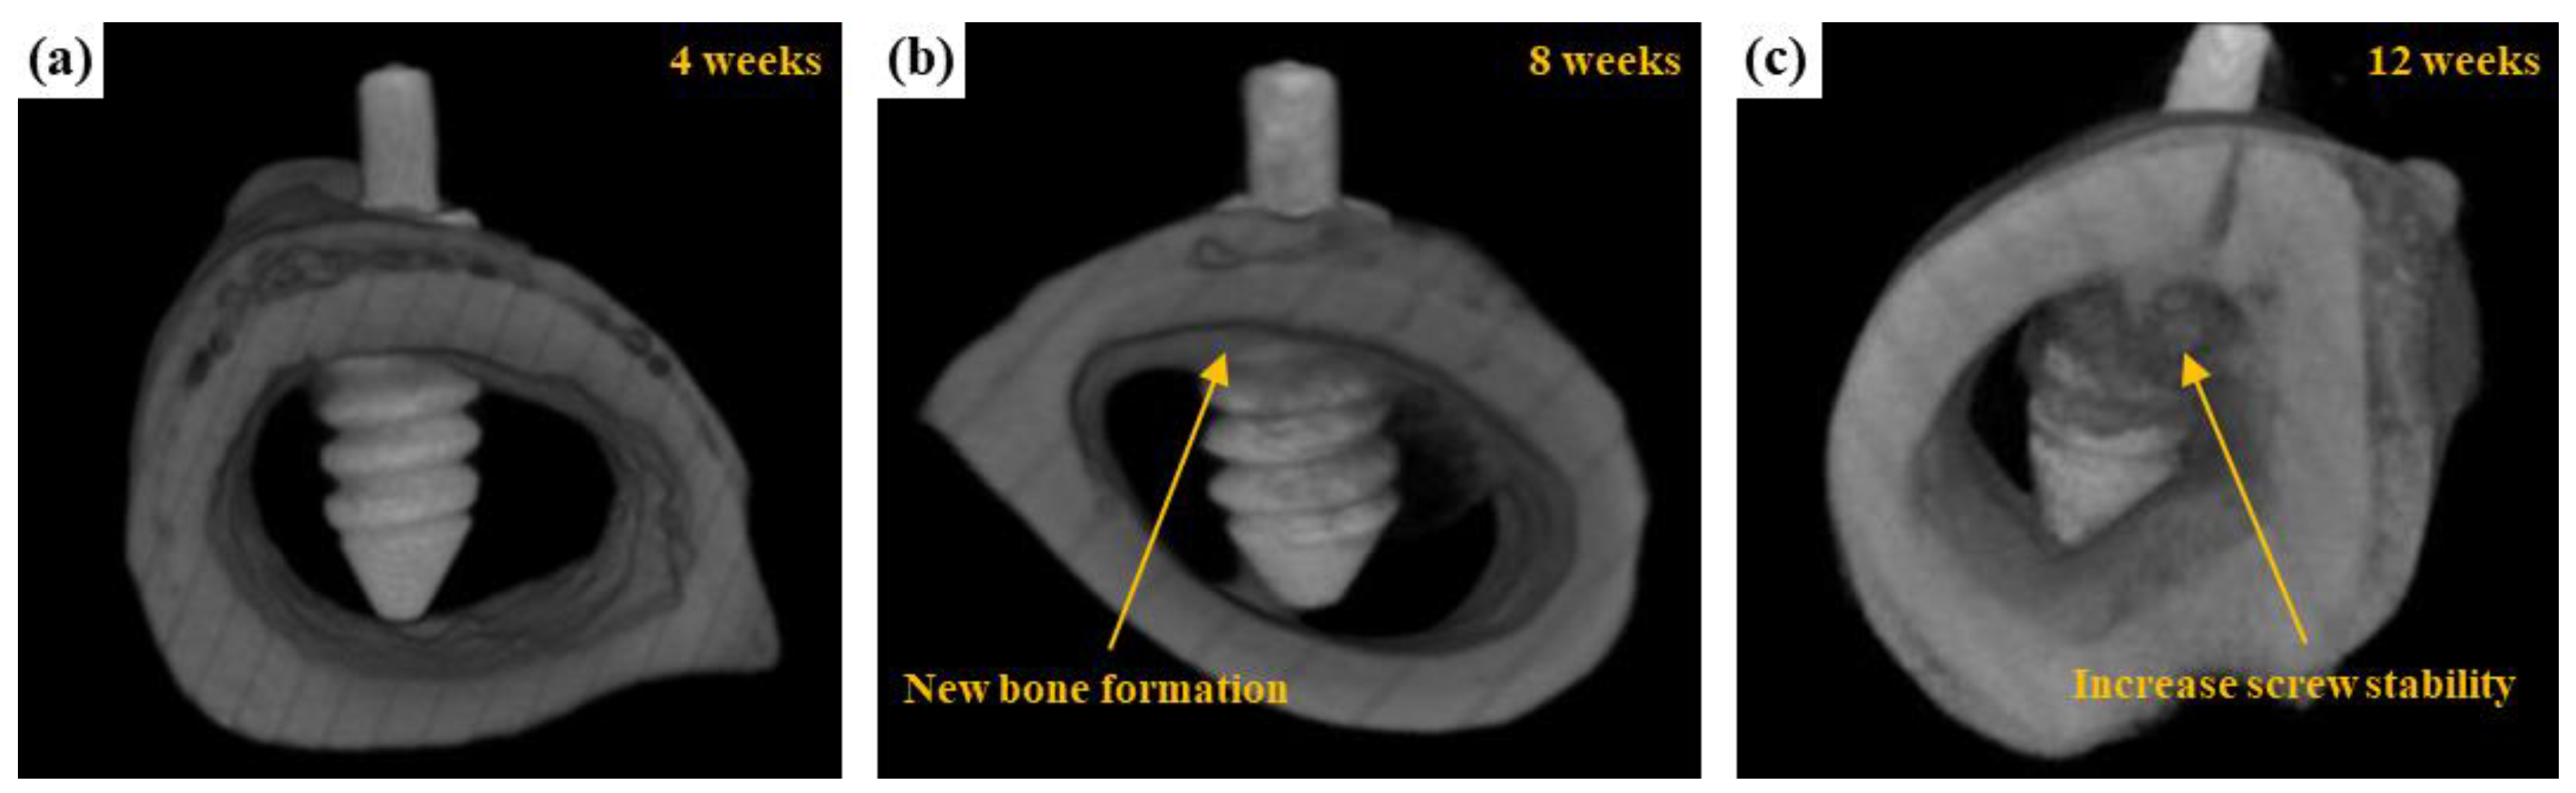

3.3. Animal Experiments

3.3.1. Radiological Examination

3.3.2. μCT Scanning